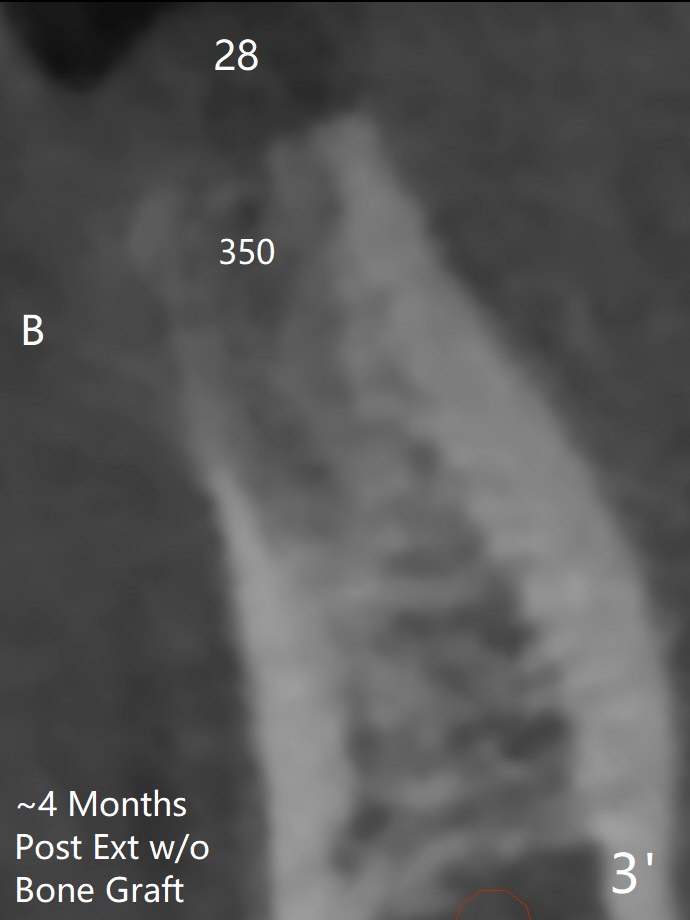

Bone Density Post Extraction with or without Bone Graft

Edentulous Lower Molar